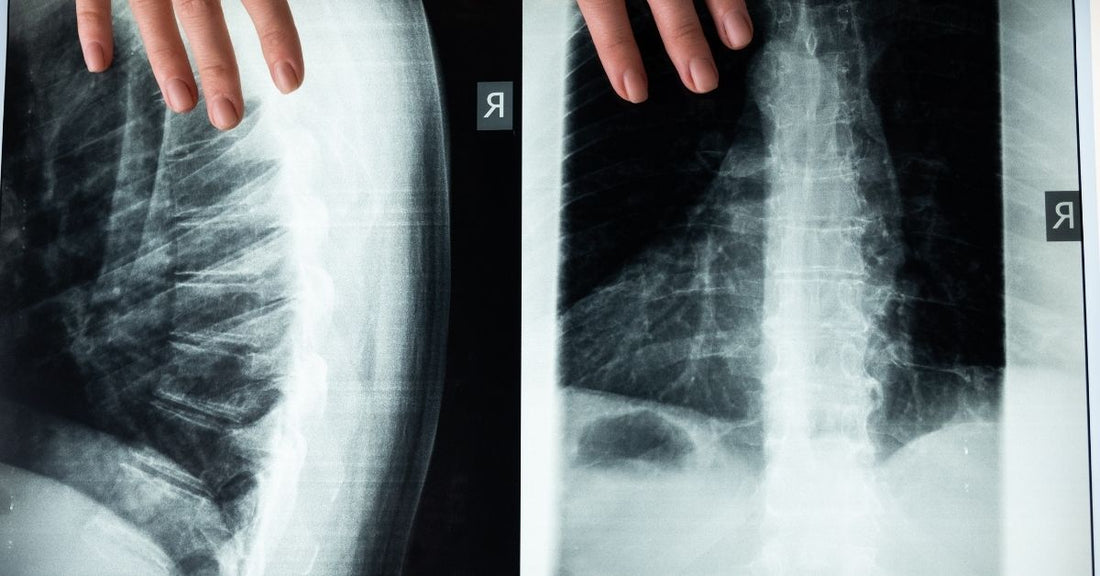

Anatomy of the spine

The spinal column is made up of 24 individual bones called vertebrae. These are divided into three sections: the cervical, the thoracic and the lumbar spine.

The cervical spine or neck is composed of the first seven vertebrae; the next 12 bones comprise the thoracic vertebrae and the remaining five are known as the lumbar vertebral, located in the lower back.